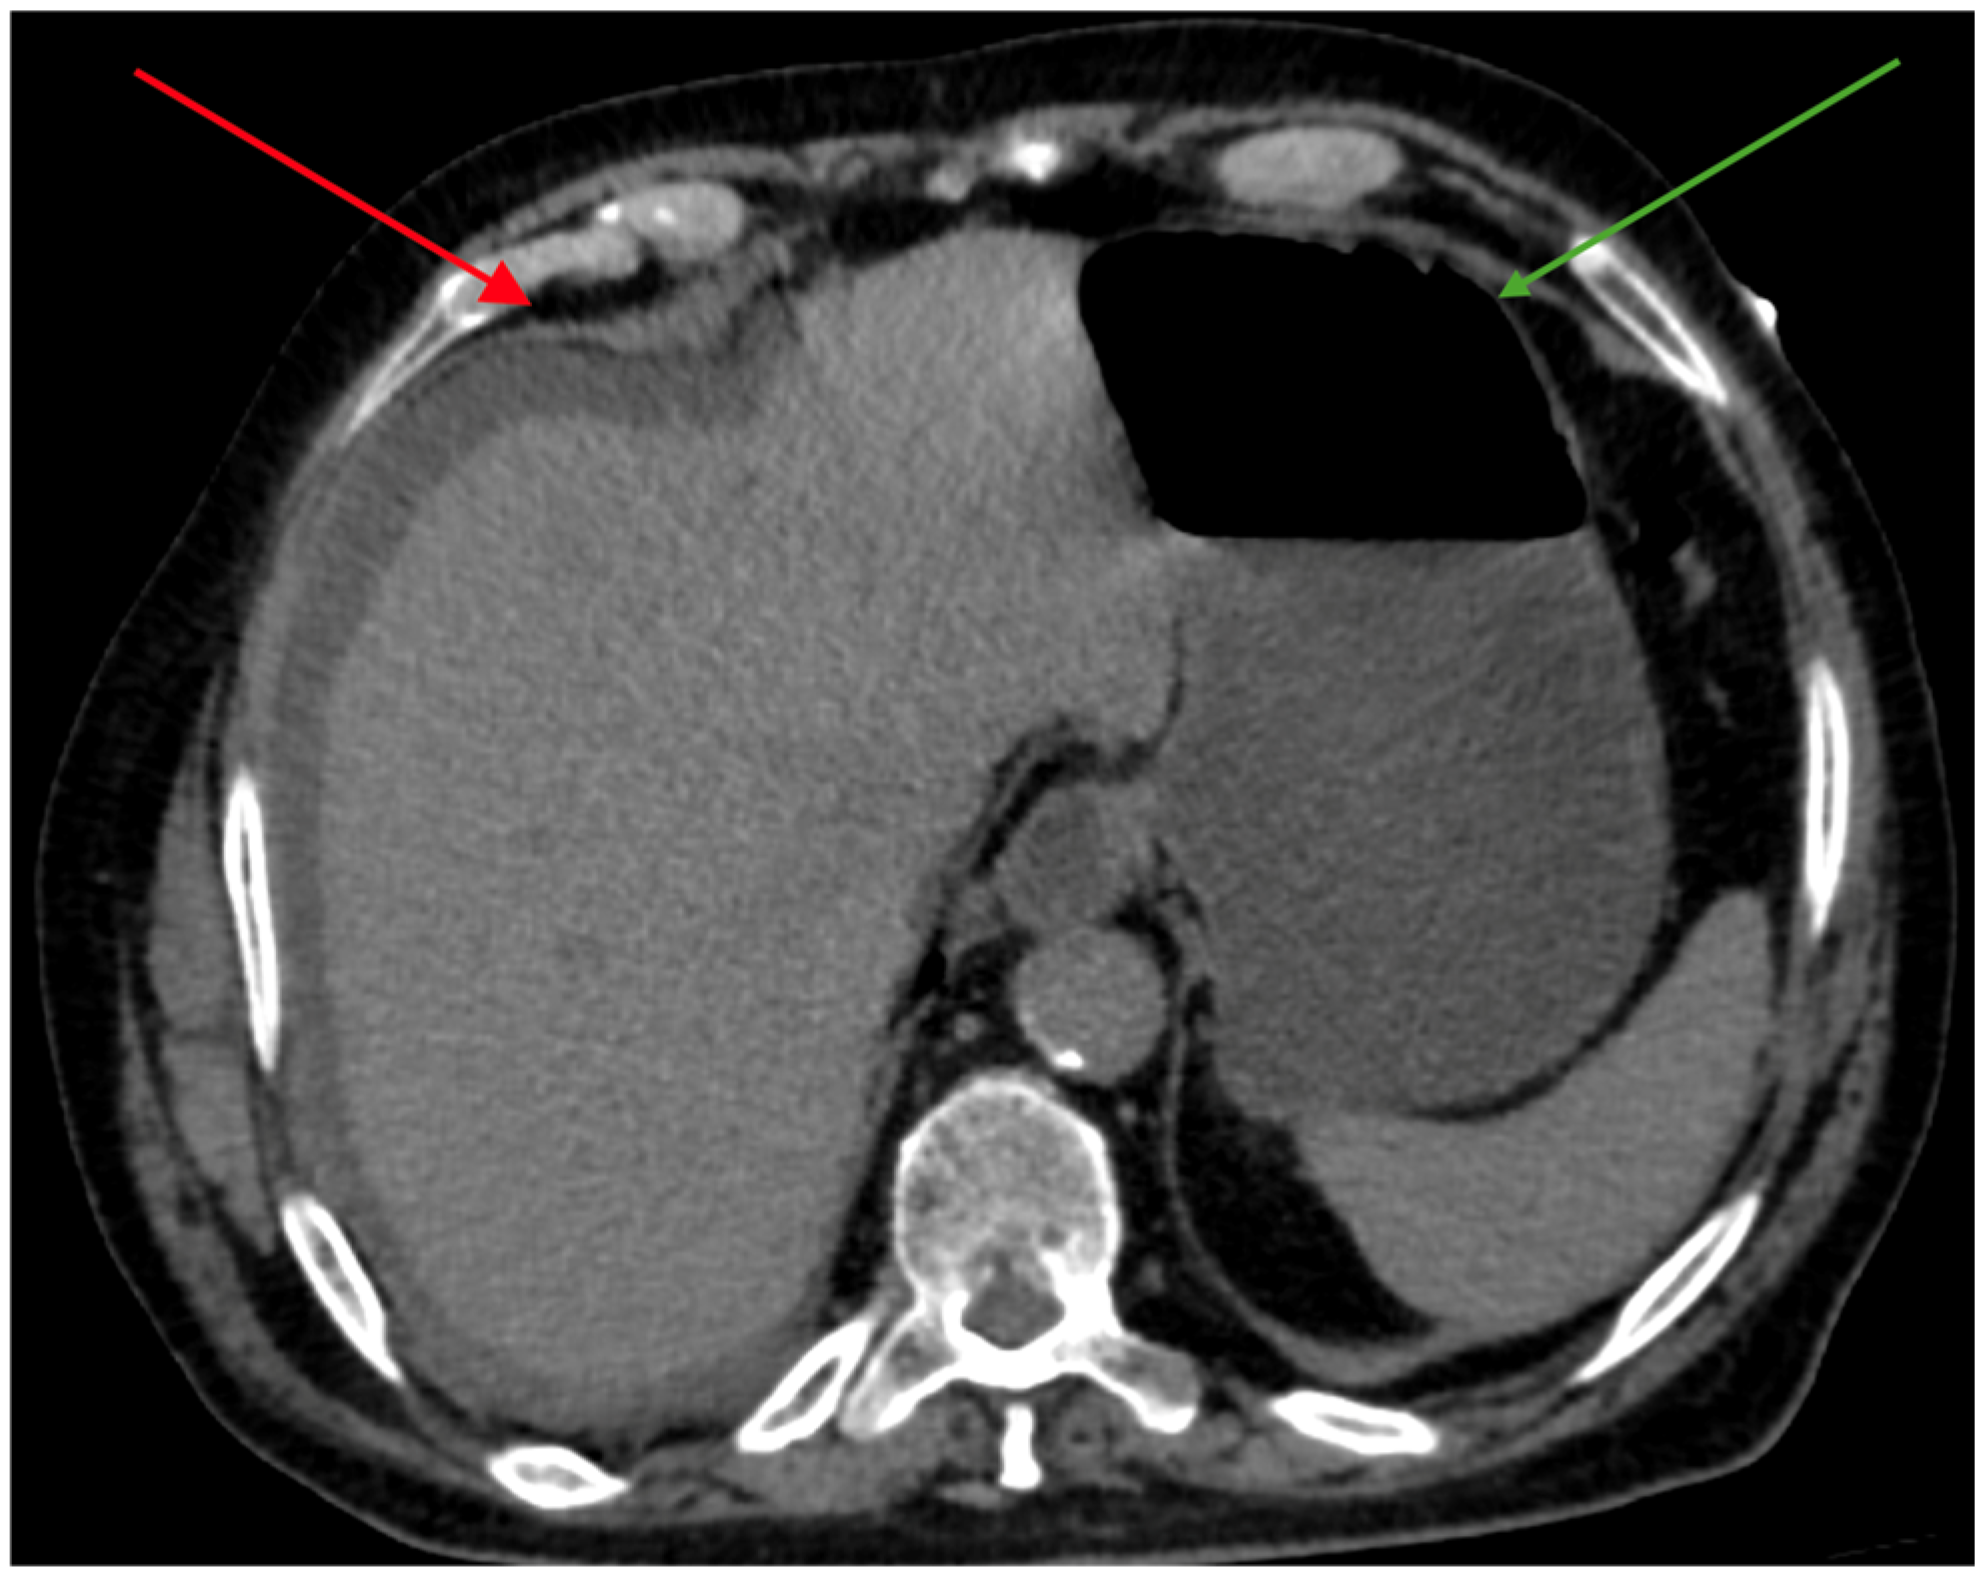

2.1.2. Admission to Emergency Unit and First Hospitalization

2.1.3. Second Hospitalization and Bile Peritonitis